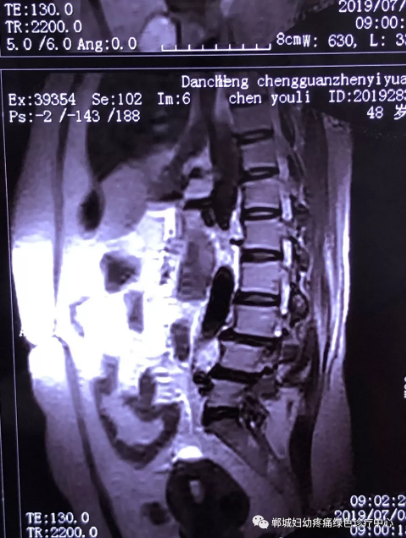

2年前,雙樓鄉(xiāng)的陳女士不小心摔了一跤后出現(xiàn)腰痛,當(dāng)時到藥店買了膏藥來貼,疼痛減輕了一些,但是從此以后反反復(fù)復(fù)出現(xiàn)腰痛。到處進行治療,不見好轉(zhuǎn),最近腰痛加重了,痛得受不了,出現(xiàn)行走后甚至持續(xù)的雙下肢后側(cè)或后外側(cè)放射性的疼痛麻木、間歇性跛行等癥狀。陳女士趕忙去醫(yī)院治療,做了磁共振檢查后確診為腰椎滑脫、腰椎反弓。醫(yī)生都告訴她需要手術(shù)治療。隨后她又帶著片子咨詢了好幾家醫(yī)院,結(jié)果都是一樣,她已經(jīng)做好了手術(shù)的打算。

治療前